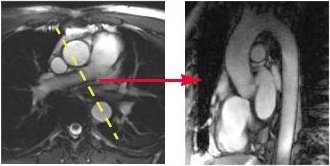

- Prescribe and acquire an axial localizer.

- Prescribe and acquire oblique sagittal slices (yellow line indicates graphic location) for an aortic arch view.

Figure 2. Oblique sagittal slice location